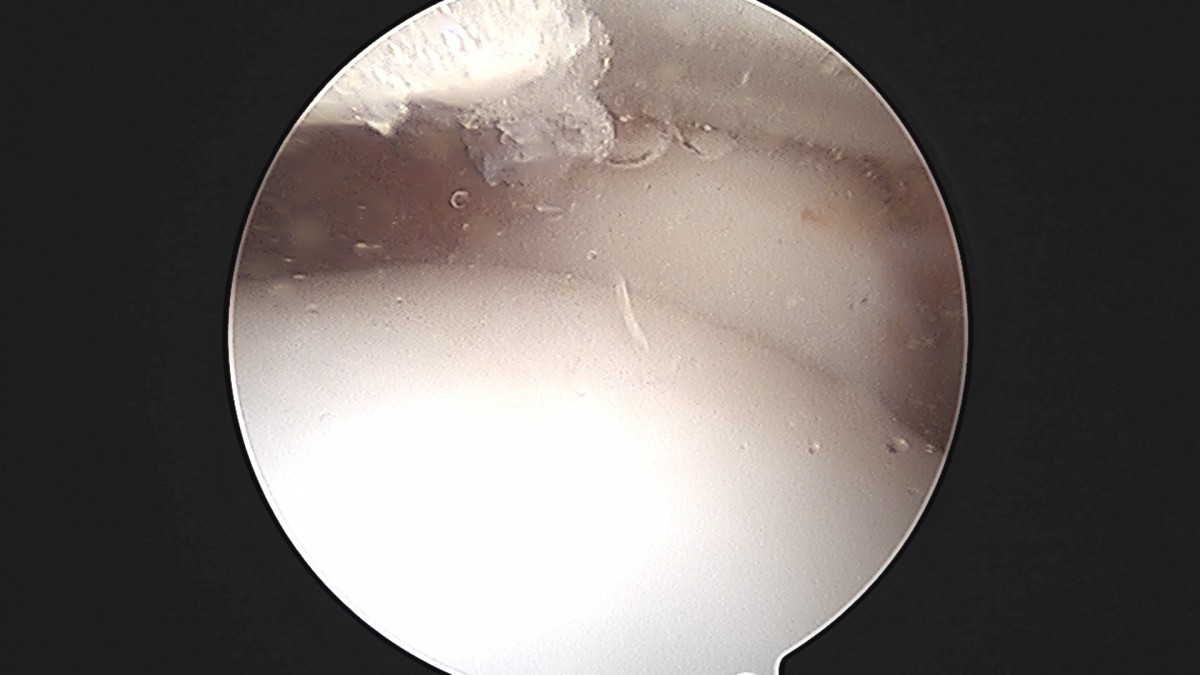

정지영원장님 발목 인대 봉합술 채이O 환자

작성자 최고관리자 댓글 0건 조회 718회 작성일 25-09-16 17:02